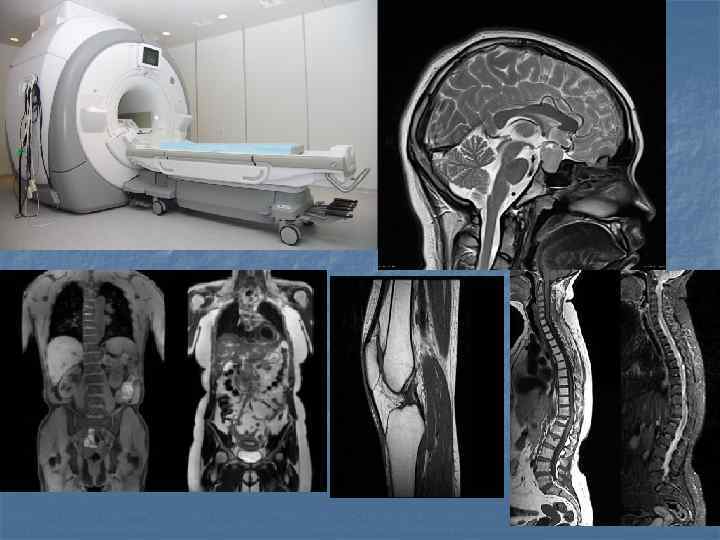

Показания n n n n Заболевания головного мозга, 2. Исследования функций отделов головного мозга, 3. Заболевания суставов, 4. Заболевания спинного мозга, 5. Заболевания внутренних органов брюшной полости, 6. Заболевания системы мочевыведения и воспроизводства, 7. Заболевания средостения и сердца, 8. Заболевания сосудов.

Показания При заболеваниях головного мозга показания к МРТ следующие: инфаркты, инсульты – для оценки масштабов поражения мозга; рассеянный склероз; дегенеративные и демиелинизирующие патологии нервной ткани; нарушения работы гипофиза; инфекционные заболевания (энцефалит и пр. ) n Магнитно-резонансная томография успешно используется для выявления патологий сосудистого русла: тромбы, аневризмы; артерио-венозные мальформации; стеноз; окклюзии; n При обследовании позвоночника имеются следующие МРТ показания: кровоизлияния в спинной мозг; стеноз позвоночного канала; компрессии спинного мозга; протрузии, грыжи межпозвоночных дисков; воспалительные заболевания спинного мозга и позвоночника; сосудистые нарушения, спинальный инсульт. n При патологиях суставов томография позволяет определить: воспалительные и инфекционные заболевания; артриты, бурситы, артрозы; дегенеративно-дистрофические изменения. n При обследовании органов грудной клетки, брюшной полости, забрюшинного пространства, малого таза метод используется для выявления: врожденных и приобретенных пороков сердца; заболеваний грудной, брюшной аорты и других сосудов; абсцессы, гематомы, воспалительные поражения печени, почек, селезенки и других органов; желчнокаменной болезни; нарушений лимфатической системы; повреждения органов после травм; инфекционные и прочие нарушения. n